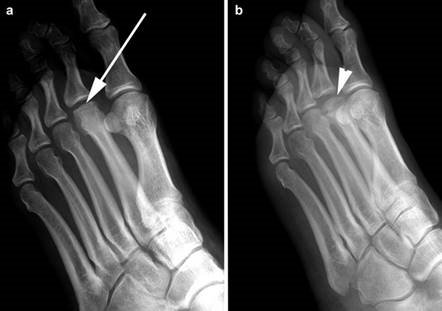

Weight-bearing anteroposterior (AP), lateral, and sesamoid axial radiographs are mandatory. On the AP view, the surgeon measures the Hallux Valgus Angle (HVA, normal < 15°), the Intermetatarsal Angle (IMA, normal < 9°), and the Distal Metatarsal Articular Angle (DMAA). The lateral view is scrutinized for Meary's angle (talo-first metatarsal angle) to identify midfoot collapse, as well as the presence of dorsal osteophytes indicative of hallux rigidus. The sesamoid axial view is critical for assessing the degree of sesamoid subluxation and the integrity of the crista.

Hallux varus, characterized by medial deviation of the hallux, is an iatrogenic complication that is deeply frustrating for both the surgeon and the patient. It is typically the result of a "staged" error: over-resection of the medial eminence past the sagittal sulcus, combined with over-plication of the medial capsule and complete transection of the lateral collateral ligament. Flexible deformities can occasionally be managed with an extensor hallucis brevis (EHB) tenodesis, while rigid deformities inevitably require arthrodesis.